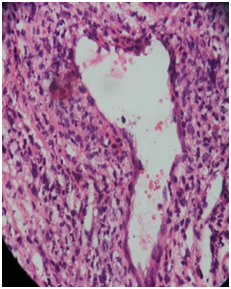

Finally the patient underwent wide local excision of the lesion and overlying necrosed skin under general anesthesia presuming it to be a pseudo tumor with super imposed fungal infection. The specimen was sent for histopathological and immunohisto chemical analysis. The H&E stained sections showed extensive necrosis, areas of hemorrhage, prominent blood vessels and multifocal cellular infiltration (Figure 4). Some of the vessels were thrombosed, and showed perivascular coagulative necrosis. The major cellular component was atypical lymphoid cells with evidence of super imposed fungal infection.

Figure 4 Showed extensive necrosis, areas of hemorrhage, prominent blood vessels and multifocal cellular infiltration.

Immuno histochemistry report were suggestive of a Non‒Hodgkin’s lymphoma of NK/T cell, nasal type with tumor cells expression of CD 3(weak), CD 2(weak), CD 56 and granzyme B. In situ hybridization of EBV RNA was positive. (SRL Diagnostics, Mumbai).